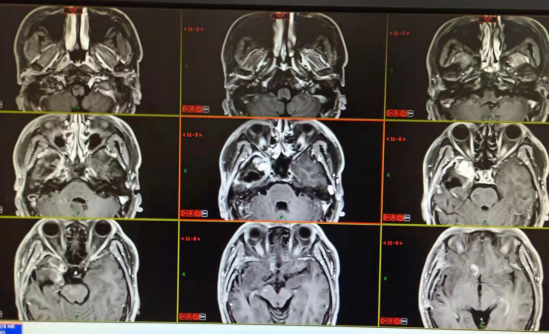

20190927郑州金水医院

20190927郑大一附院:右侧颞叶巨大占位,考虑胶质瘤。

术后MRI:20191005郑大一附院:“右颞部占位切除术”后改变。

放化疗后MRI:20191020西安交大

20200220三门峡黄河医院:右侧颞叶胶质瘤术后,右侧局部脑膜增厚,术区未见明显异常强化。

20200512三门峡市中心医院:右颞部胶质瘤术后改变,硬膜下积液。

2020.07.30三门峡市中心医院:右侧颞叶胶质瘤术后改变,右侧颞叶异常强化影,与0512日片对比强化灶较前明显,大小无明显变化。

2020.09.01右侧颞部胶质瘤术后改变,颞叶病灶强化程度较前减弱。左侧颞部结节状强化影,大致同前。

2020.12.08三门峡市中心医院:右侧颞叶胶质瘤术后改变,病变范围较前增大,新见脑桥、右侧额叶强化,考虑肿瘤复发可能。

2021.01.08三门峡市中心医院:右侧颞叶胶质瘤术后改变,右额叶病灶较前增多,原脑干、右侧额叶病灶较前体积增大,考虑肿瘤进展。